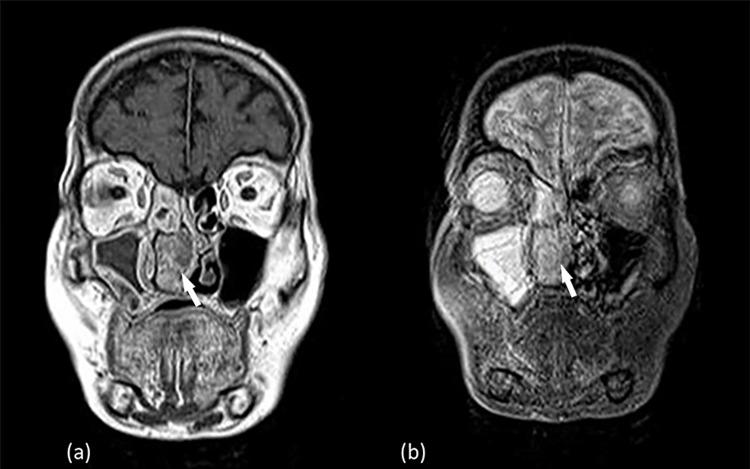

Sinonasal mucosa is an area of high melanocyte density compared to other mucosa-lined sites. Sinonasal mucosal melanomas (SNMM) most commonly arise from the nasal cavity and the paranasal sinuses. Due to their obscure anatomic location and lack of early symptomatology, SNMM are often diagnosed in an advanced stage. The majority of patients who present with symptoms complain of unilateral nasal dysfunction, such as obstruction and epistaxis. We hereby report a case of an 86-year-old female, who presented with a three-year history of progressive right-sided nasal obstruction and recurrent epistaxis. Posterior rhinoscopy and endoscopy revealed a polypoid, fleshy lesion whose coloration varied from mildly pigmented to amelanotic. Inverted sinonasal papilloma was included in the differential diagnosis due to MRI findings. Post-resection histopathology indicated a mucosal melanoma. Typically, amelanotic lesions are rare, more difficult to diagnose and associated with worse prognosis due to both their aggressiveness and delayed diagnosis.

与其他有黏膜衬里的部位相比,鼻窦黏膜是黑素细胞密度较高的区域。鼻窦黏膜黑色素瘤(SNMM)最常起源于鼻腔和鼻窦。由于其解剖位置隐匿且缺乏早期症状,SNMM常被诊断为晚期。出现症状的大多数患者主诉单侧鼻功能障碍,如鼻塞和鼻出血。我们在此报告一例86岁女性患者,她有三年进行性右侧鼻塞和反复鼻出血的病史。后鼻镜检查和内镜检查发现一个息肉样、肉质病变,其颜色从轻度色素沉着到无色素沉着不等。由于MRI检查结果,鉴别诊断中包括了内翻性鼻窦乳头状瘤。切除术后组织病理学显示为黏膜黑色素瘤。通常,无色素沉着的病变很少见,更难诊断,并且由于其侵袭性和诊断延迟,预后较差。